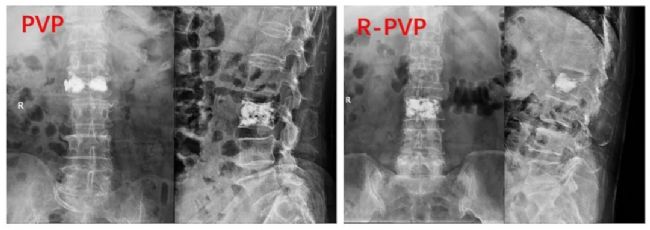

④兩組之間骨水泥彌散的程度:使用ImageJ軟件評估骨水泥的彌散程度,結(jié)果分為四類:I度代表骨水泥在正側(cè)位片上的覆蓋面積均小于50%;Ⅱ度代表骨水泥在正位或側(cè)位片上的覆蓋面積大于50%小于75%;Ⅲ度代表骨水泥在正側(cè)位片上的覆蓋面積均大于50%小于75%;IV代表骨水泥在正側(cè)位片上的覆蓋面積均超過75%,兩組間差異有統(tǒng)計學(xué)意義。

術(shù)后X線顯示骨水泥的彌散。與PVP組相比,R-PVP組在術(shù)后X線片上表現(xiàn)出更強的在椎體中線的融合能力。